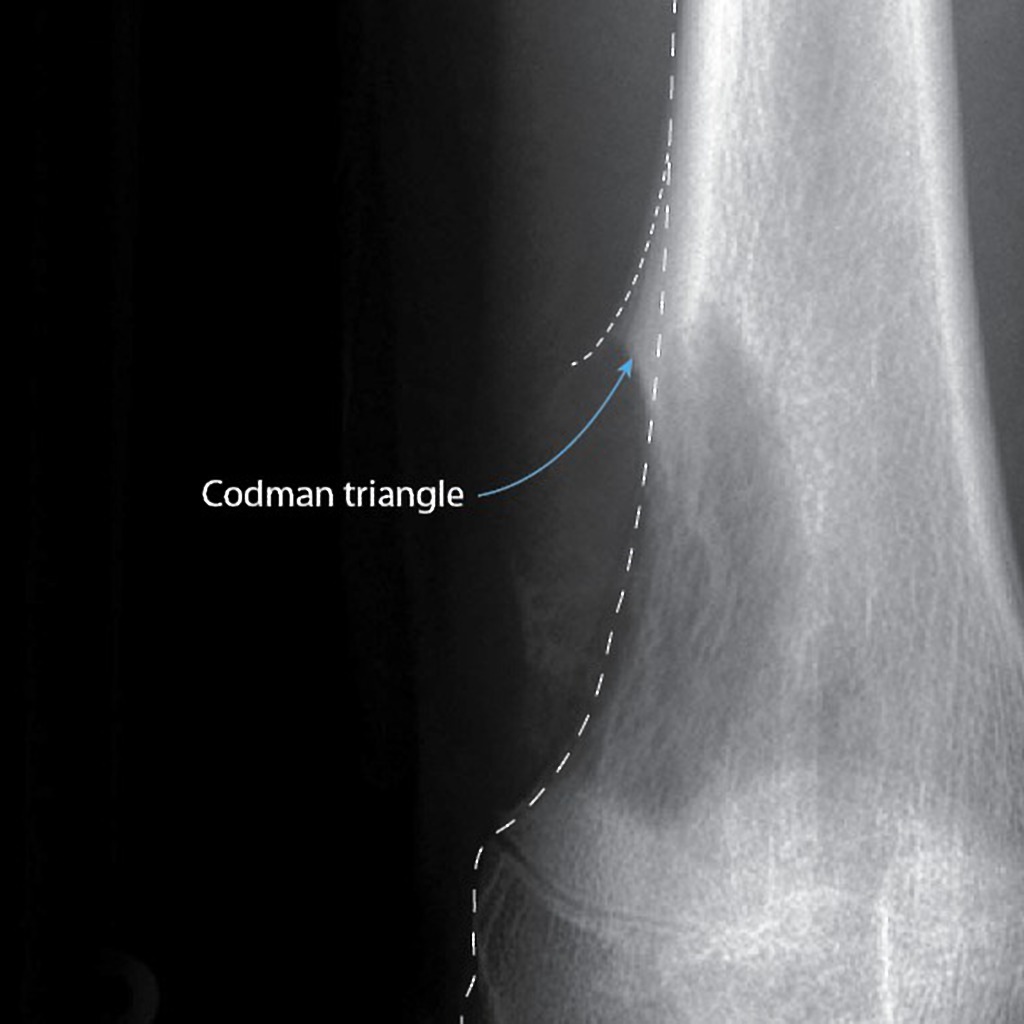

Codman’s Triangle

Definition – triangular area of new subperiosteal bone that is created when a bone tumor raises the periosteum away from the healthy bone

Clinical Significance – this occurs because the tumor is growing at a faster rate than the periosteum can expand, which leads to the periosteum tearing away and providing a second edge of ossification (thus making the triangle). Presence of this finding is highly suggested of a fast growing, malignancy.